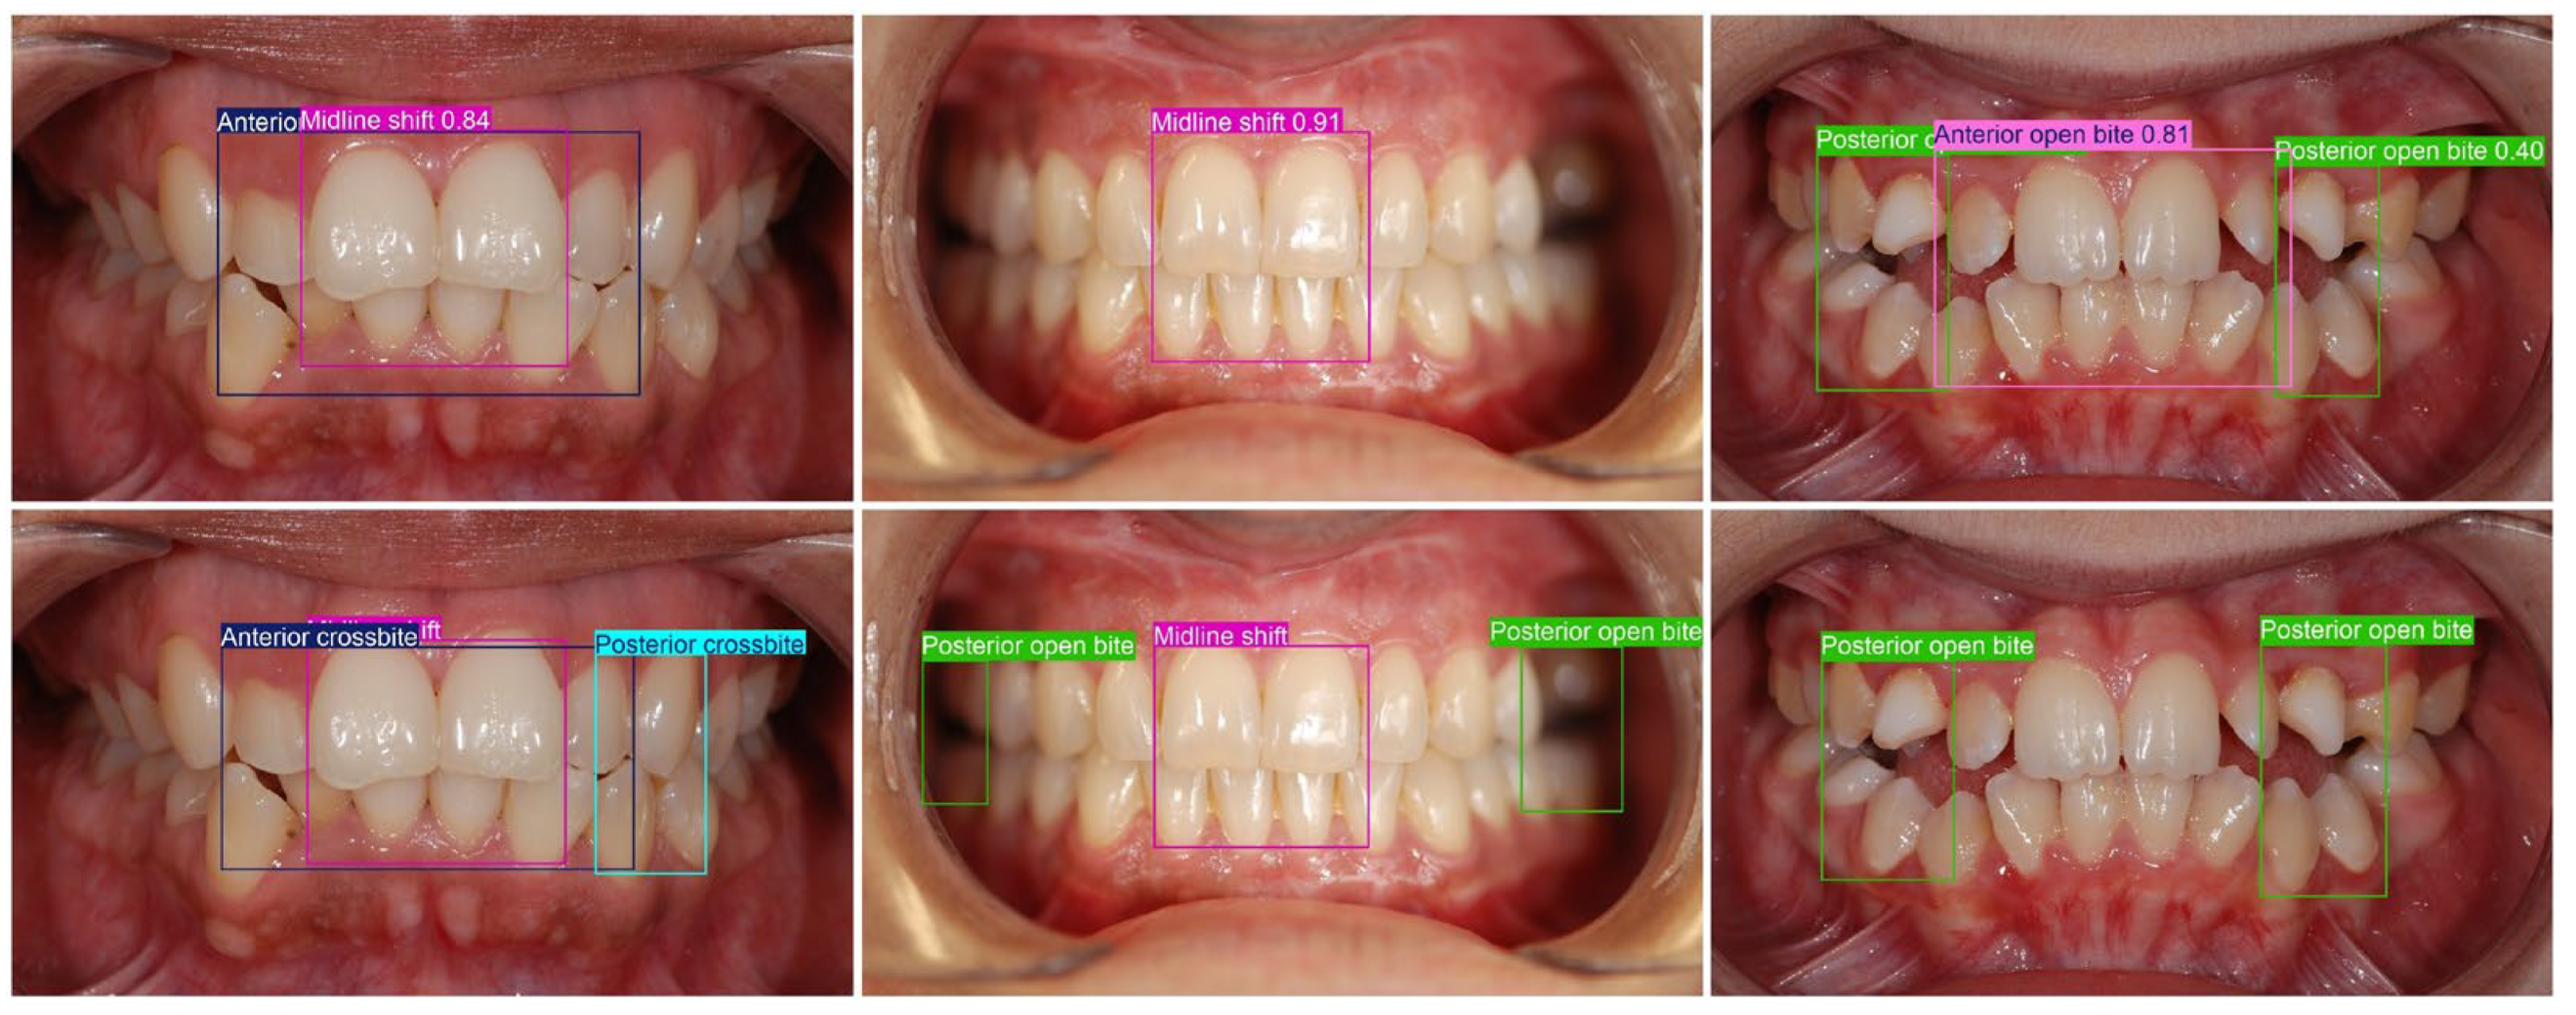

| Big overjet, Anterior crossbite, Deep bite, Head bite, Anterior open bite | BB over the four upper incisors as well as the overlapping lower canines and incisors |

| Midline shift | BB over the upper central incisors as well as the overlapping lower incisors and canines |

| Anterior crossbite | One or more maxillary incisors occlude lingual/palatal to the mandibular incisors |

| Anterior open bite | No vertical overlap of anterior teeth in occlusion; a visible gap remains between upper and lower incisors when posterior teeth are in contact |

| Midline shift | The upper and lower dental midlines do not coincide (visible mismatch between the contact points of the central incisors) |

| Posterior crossbite | One or more posterior teeth occlude in reverse transverse relationship: maxillary posterior teeth are positioned lingual/palatal to mandibular posterior teeth |

| Posterior open bite | No occlusal contact in the posterior segment despite attempted occlusion; a visible vertical gap between posterior antagonists |